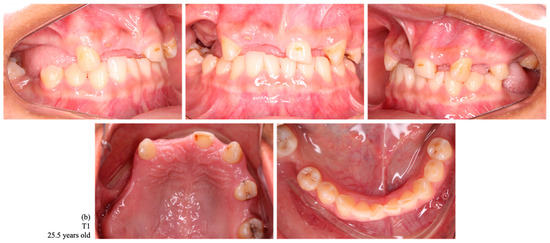

Figure 3.

Intraoral photographs of dental occlusion of a female indigenous participant, a habitant of the Arara village, with no tooth loss at T0 (a) and with a loss of 12 permanent teeth at T1 (1.7, 1.6, 1.5, 1.4, 1.2, 1.1, 2.2, 2.4, 2.6, 3.7, 3.6, and 4.6) (b).